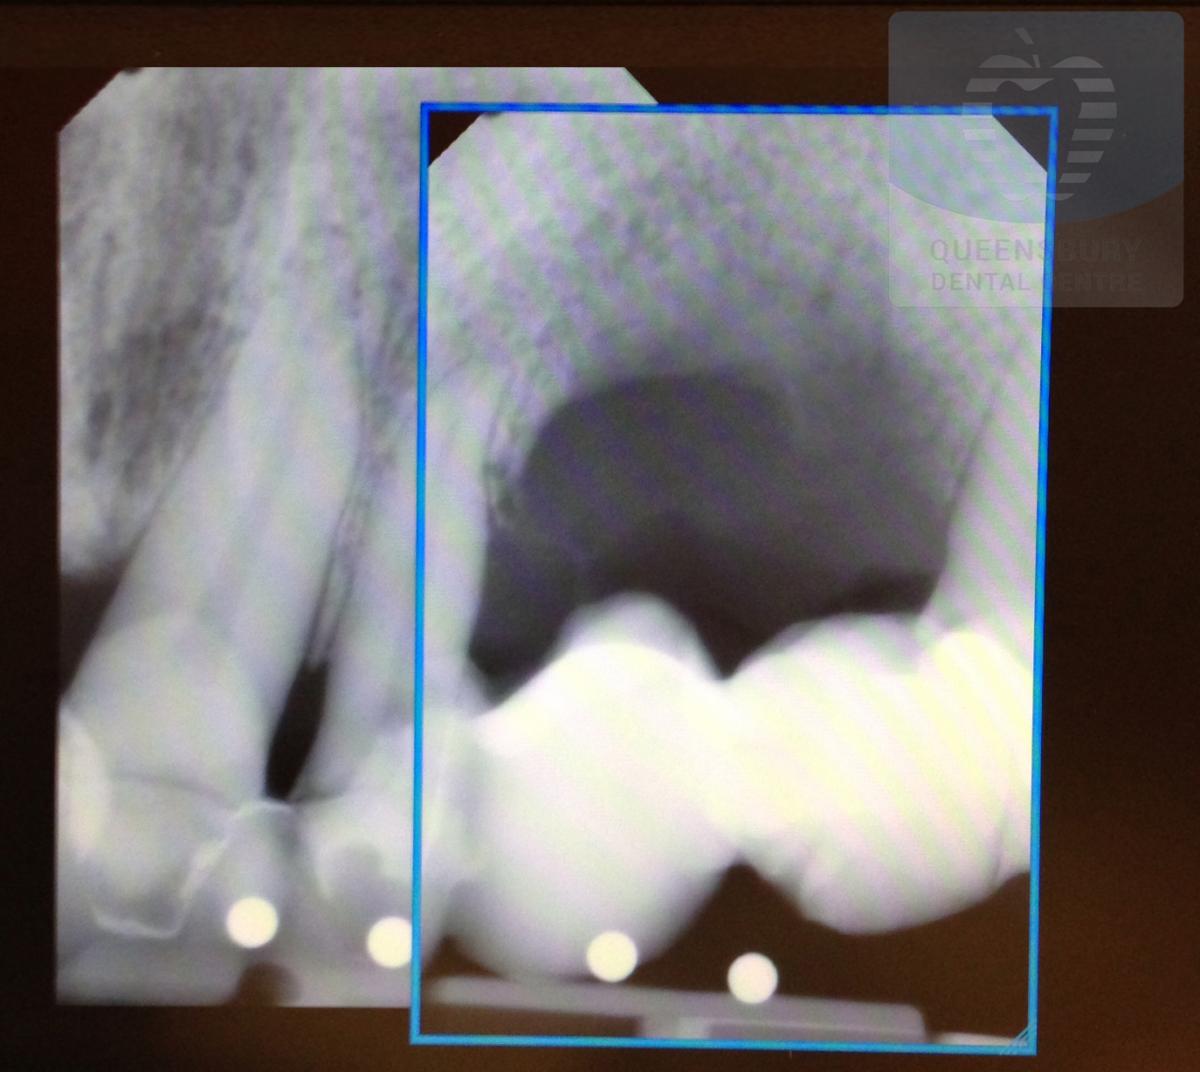

Implants Placed & Restored By Our Queensbury Doctors

Missing teeth and loose dentures make many people avoid social settings because they are too self-conscious about their appearance. Current dental procedures, however, replace everything from a single missing tooth to a completely missing arch. Ask your dentist or dental specialist about the different dental options that are available to you. Don’t let another day go by without taking this important first step to restoring your confidence and your smile!